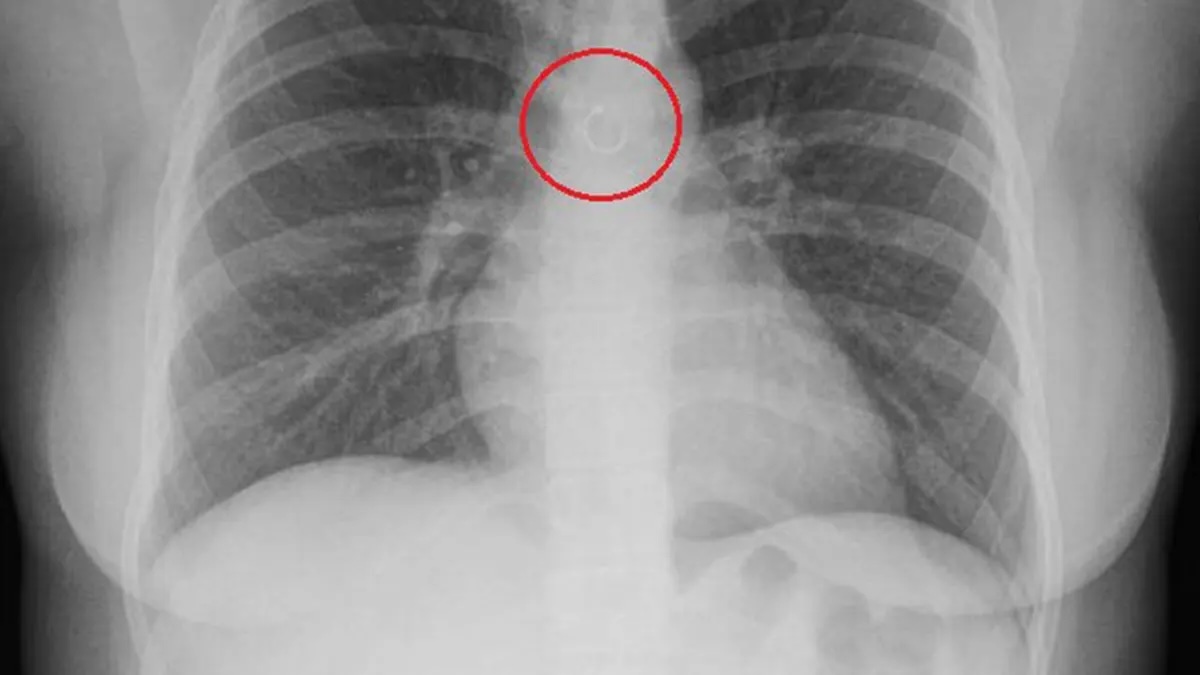

Theo trang Oddity Central (Anh), Monica Deyanira Cabrera Barajas, 26 tuổi, bắt đầu bị ho khó chịu kéo dài khoảng một tháng rồi mới quyết định đi khám. Cô nghĩ rằng phim chụp X-quang sẽ chỉ ra một vấn đề hô hấp thông thường, nhưng hoàn toàn không ngờ thứ xuất hiện trên ảnh lại chính là chiếc khuyên mũi.

Từ ngỡ ngàng, cô nhanh chóng chuyển sang lo sợ khi các bác sĩ cho biết chiếc khuyên kim loại dạng vòng chỉ cách động mạch chủ khoảng 0,5 mm. Cô Deyanira lập tức được chỉ định phẫu thuật khẩn cấp. Tuy nhiên, ca mổ dự kiến kéo dài 20 phút lại kéo dài gần một tiếng rưỡi và không thành công.

Ảnh chụp X-quang cho thấy chiếc khuyên mũi mắc kẹt trong phổi. Ảnh: O.C

May mắn, ca mổ thứ hai đã thành công. Các bác sĩ nhận định cô cực kỳ may mắn khi còn sống. Nếu chiếc khuyên kim loại làm thủng phổi hoặc mạch máu lớn nhất cơ thể, hậu quả có thể là xẹp phổi hoặc vỡ động mạch chủ - những biến chứng có nguy cơ tử vong cao.